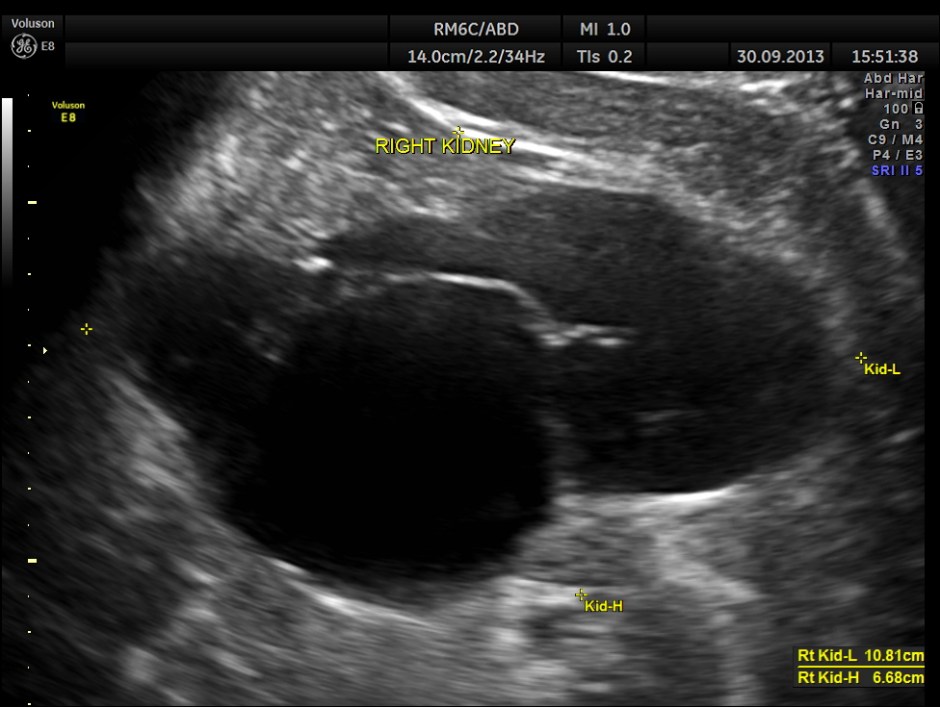

the right kidney showed moderate to severe hydro-nephrosis

the following images show the 2 d and 3 d appearance of the same.